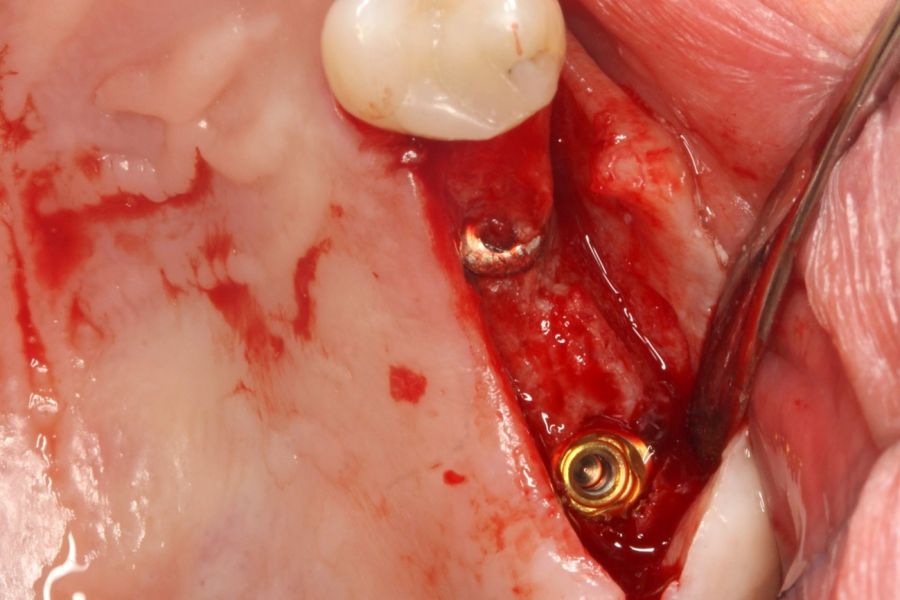

El acceso final a la cortical sinusal se efectuó con una fresa específicamente diseñada para esta técnica (fresa de corte frontal), la cual permite la eliminación controlada del suelo del seno maxilar sin comprometer la integridad de la membrana de Schneider10. Una vez expuesta la membrana a través de la perforación en la cresta ósea, se realizó su elevación de manera controlada, colocándose el injerto consistente en hueso autólogo obtenido del fresado de otras localizaciones en las que se colocan implantes en el mismo acto quirúrgico embebido en PRGF-Endoret. Por último, la colocación del implante se llevó a cabo con un motor quirúrgico calibrado a 25 Ncm y 25 rpm, mientras que la inserción final se realizó manualmente mediante una llave dinamométrica para asegurar una fijación óptima (Figura 1).

En las Figuras 7- 13 se muestra uno de los casos incluidos en el estudio.